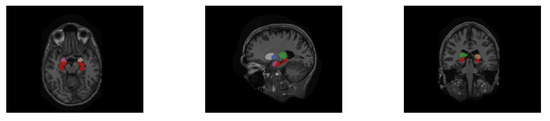

For convenience of display, the segmentation labels are mapped in the original images with the same resolution between the raw MRI image and its hippocampus segmentation label in the HarP and the MICCAI datasets. We set the corresponding hippocampus label pixel in the original MRI image to a specific value to represent the hippocampus, and other non-hippocampus pixels were kept unchanged to distinguish them from the hippocampus. The visualization segmentation results of the HarP and MICCAI datasets are displayed in Figure 6 and Figure 7, respectively. The area with a red pixel represents where the hippocampus is located, and other pixel values are non-hippocampus areas.

Figure 6. Three different dimensional slices of the hippocampus segmentation labels on the HarP dataset.